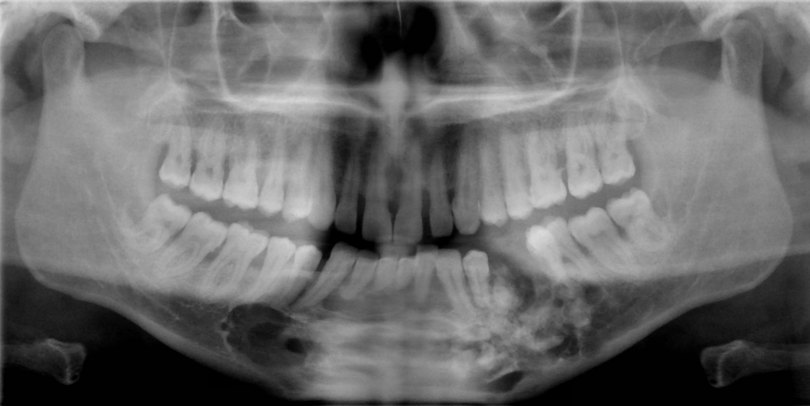

- Ακτινογραφικά, ο όγκος απεικονίζεται σαν μικτή οστεολυτική – οστεοπλαστική αλλοίωση, συχνά με σαφή όρια. Εντός της οστεόλυσης παρατηρούνται πολλές διάσπαρτες ακτινοσκιερές εστίες ποικίλου μεγέθους και πυκνότητας.

- Μπορεί να προκαλέσει μετατόπιση των παρακειμένων δοντιών και απορρόφηση των ριζών τους.